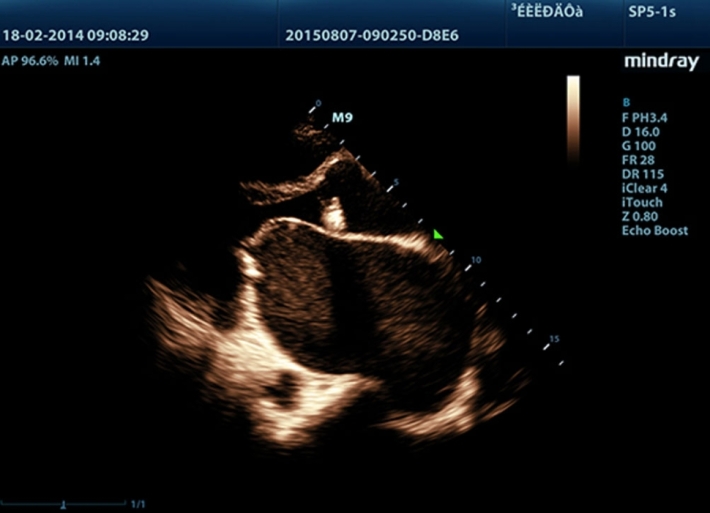

Медицинское оборудование и сервисное обслуживание